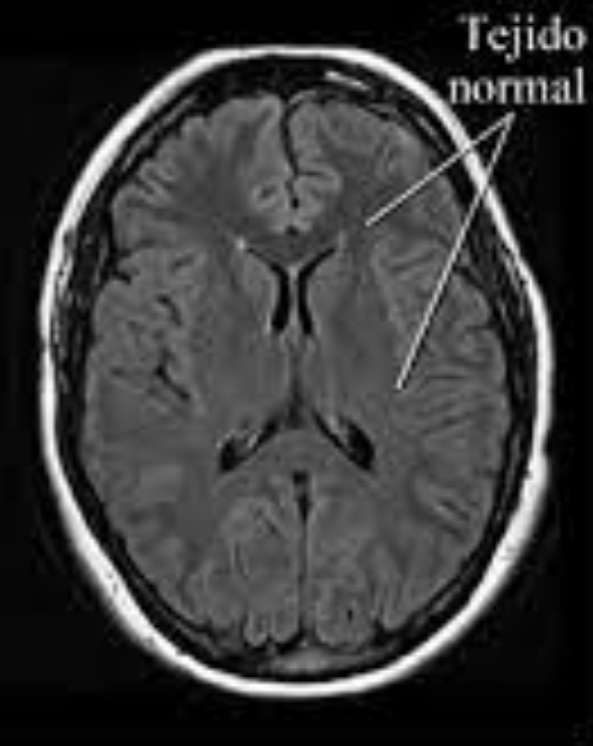

Las neuroimágenes son fundamentales para clasificar las epilepsias según etiologías o causas. La Resonancia Nuclear Magnética de Cerebro (RNM) es el «standard de oro», pero debe realizarse con un protocolo especial para epilepsia. Permite diagnosticar malformaciones, alteración de la migración neuronal, tumores y/o secuelas de enfermedades infecciosas como meningitis, encefalitis, entre otras causas.

Resonancia nuclear Magnética cerebral, que muestran tejido normal (figura 1) y tejido anormal (provocado por una lesión) que puede causar crisis epilépticas (figura 2).